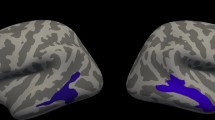

Nonparametric Spearman correlations showed no association of fetal STS depth asymmetry with later language lateralization in the overall brain (LI global R = −0.28, p = 0.203) nor with the language lateralization LIs of specific regions of interest (LI frontal R = −0.13, p = 0.146; LI temporal R = −0.04, p = 0.848; LI parietal R = −0.106, p = 0.631). However, second level multiple regression analyses of fMRI language activations, analyzed with SPM and adjusted for age at test and MR device used, revealed a significant association of the LIs of the fetal STS depth with activations in the left superior temporal lobe (Fig. 2). Thus, children with less right lateralization of the fetal STS depth showed significantly more left temporal language localization 6–13 years later.